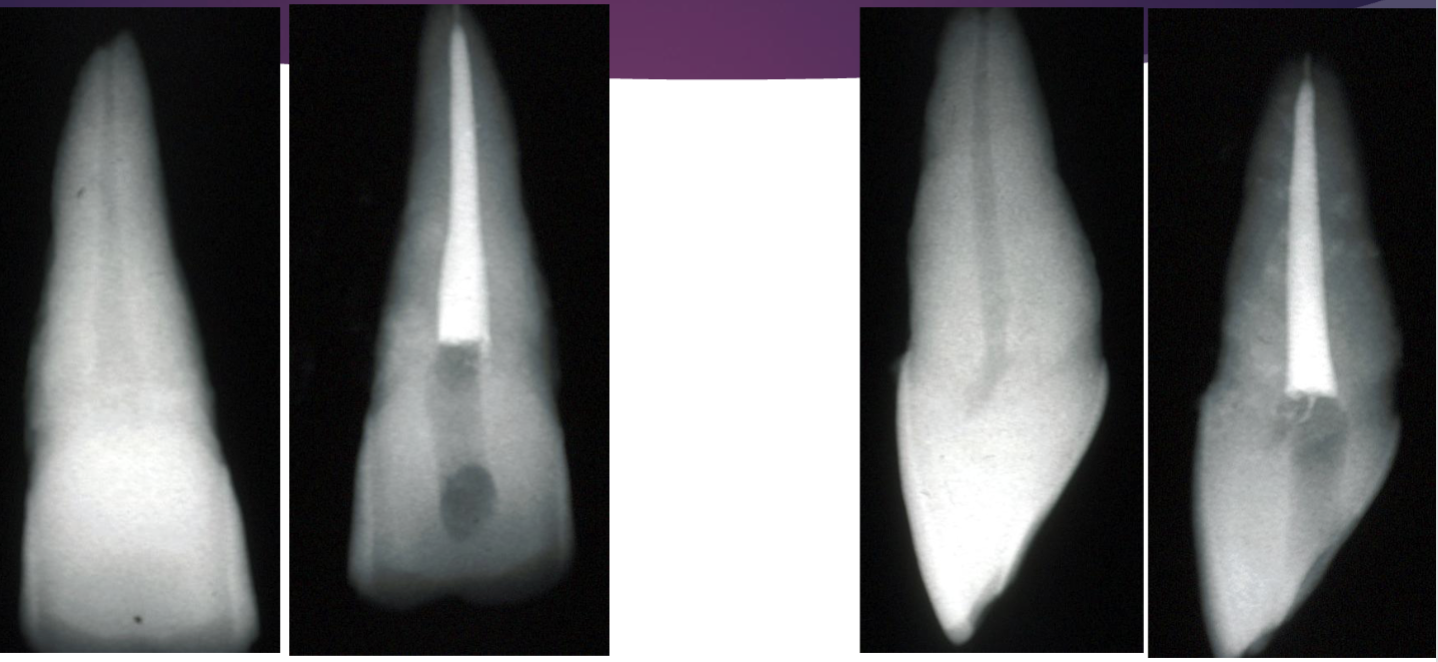

what error happen here

gouge towards the facial → opening too far

what error happened here

pulp horn not incorporated w access (was not removed)